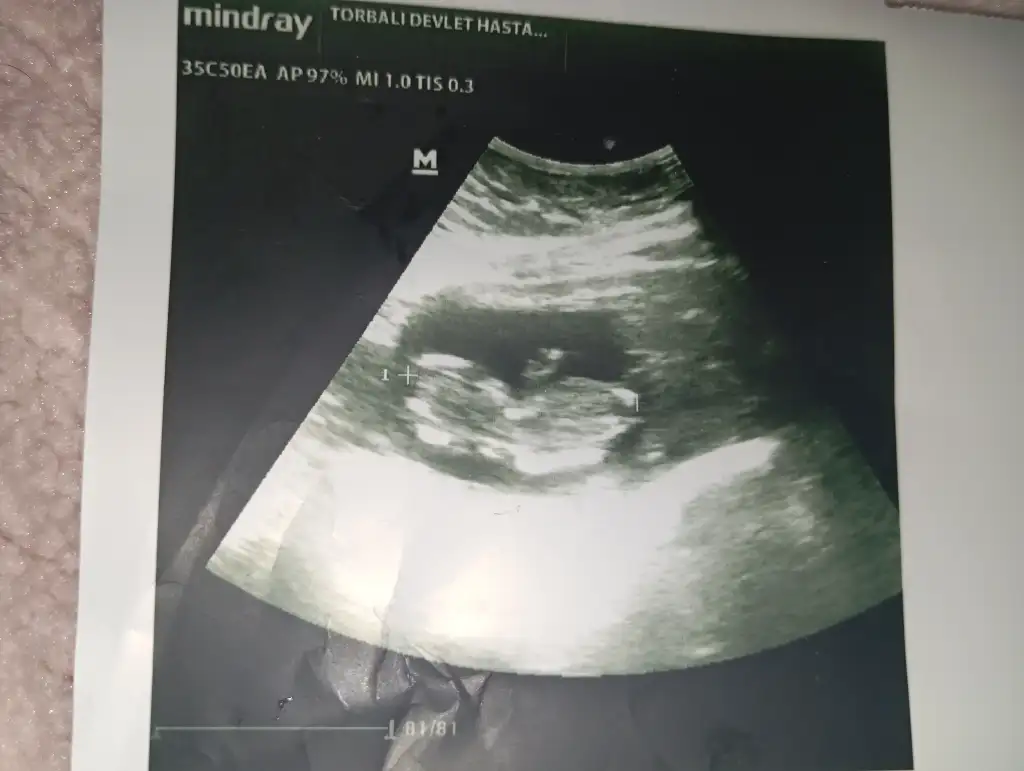

Canım erkeğe benziyor belli mi simdi cinsiyeti ne zaman belli olacakMerhaba kızlar cinsiyet tahmini yapabilen var mı acaba 13 haftalık ikiz gebelik birinin cinsiyeti öğrendik ama bu miniginkini doktorumuz daha var dedi. Tahminleri alayım? Eki Görüntüle 3582600

Alttaki erkek üstteki kız gibi geldi banaMerhaba kızlar cinsiyet tahmini yapabilen var mı acaba 13 haftalık ikiz gebelik birinin cinsiyeti öğrendik ama bu miniginkini doktorumuz daha var dedi. Tahminleri alayım? Eki Görüntüle 3582600